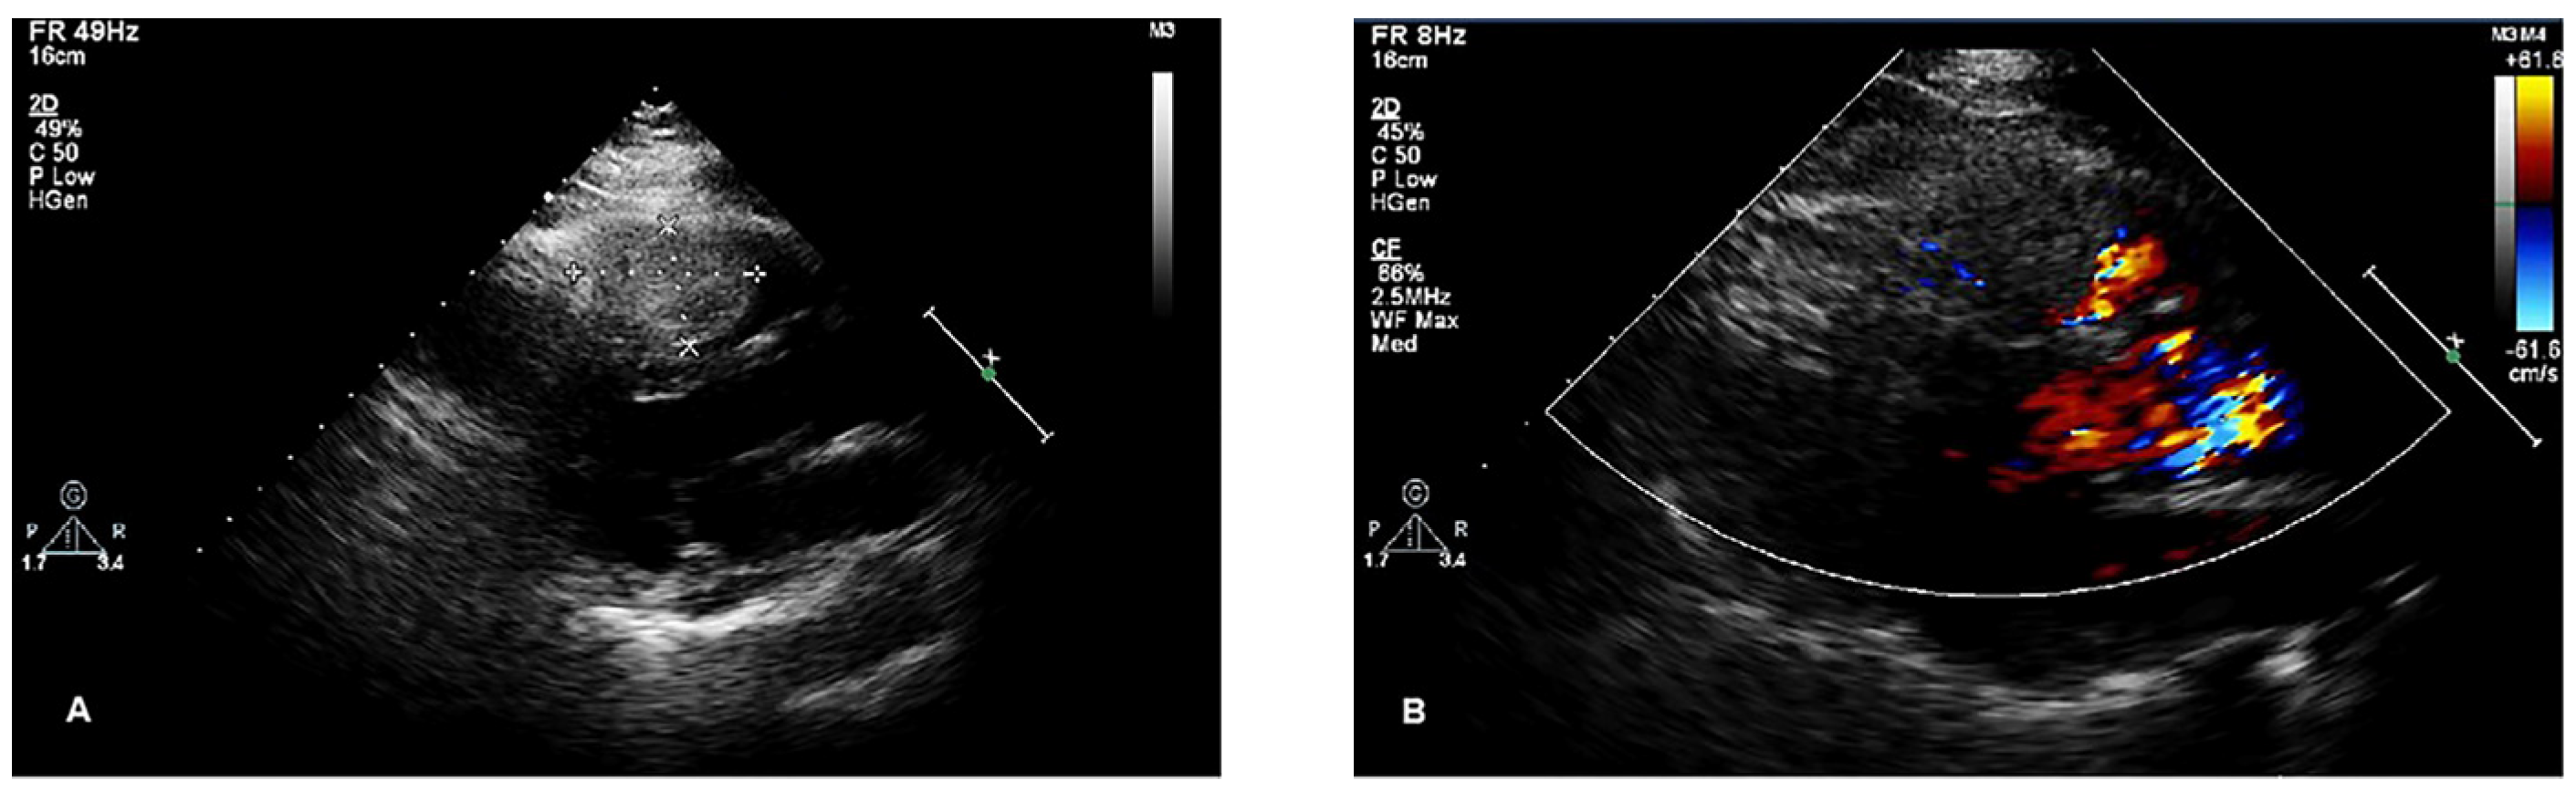

A right ventricular mass was accidentally identified in a 56-year-old woman during chest CT for a respiratory infection at a local hospital. Transthoracic echocardiogram (TTE) revealed a cardiac mass, and the patient was admitted to our hospital for further diagnosis and treatment. The patient had a history of hypertension but no history of coronary artery disease. A grade 2/6 systolic murmur was heard between the second and third intercostal spaces at the left sternal border. The electrocardiogram showed sinus rhythm with possible right bundle branch block, and chest X-ray revealed a normal-sized heart. TTE indicated that the right ventricle was of normal size. A 43 × 28 mm mass with a moderate echo appearance, neither mobile nor pedunculated, was found to be adherent to the interventricular septum and extended to the right ventricular outflow tract. In addition, mild tricuspid regurgitation and normal mitral and aortic valves were noted (Figure 1).

Figure 1.

Transthoracic echocardiography of the lesion. (A) A 43 × 28 mm mass with medium echo appearance, neither mobile nor pediculated, adhering to the interventricular septum and extending to the right ventricular outflow tract. (B) Color Doppler flow imaging (CDFI): no significant blood flow signal was detected in the mass, and slight aliasing was noted in the right ventricular outflow tract.